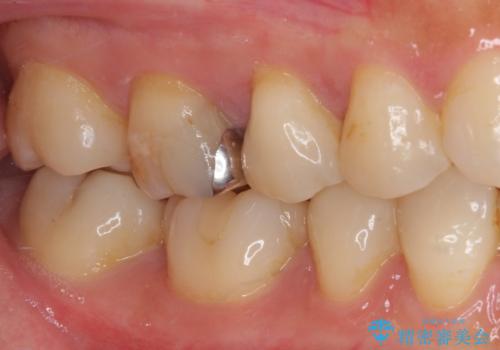

処置後に痛みを感じることはなく、冷たいものがしみることもなくなりました。

奥の大臼歯にもむし歯があったので、一緒に処置を行いました。